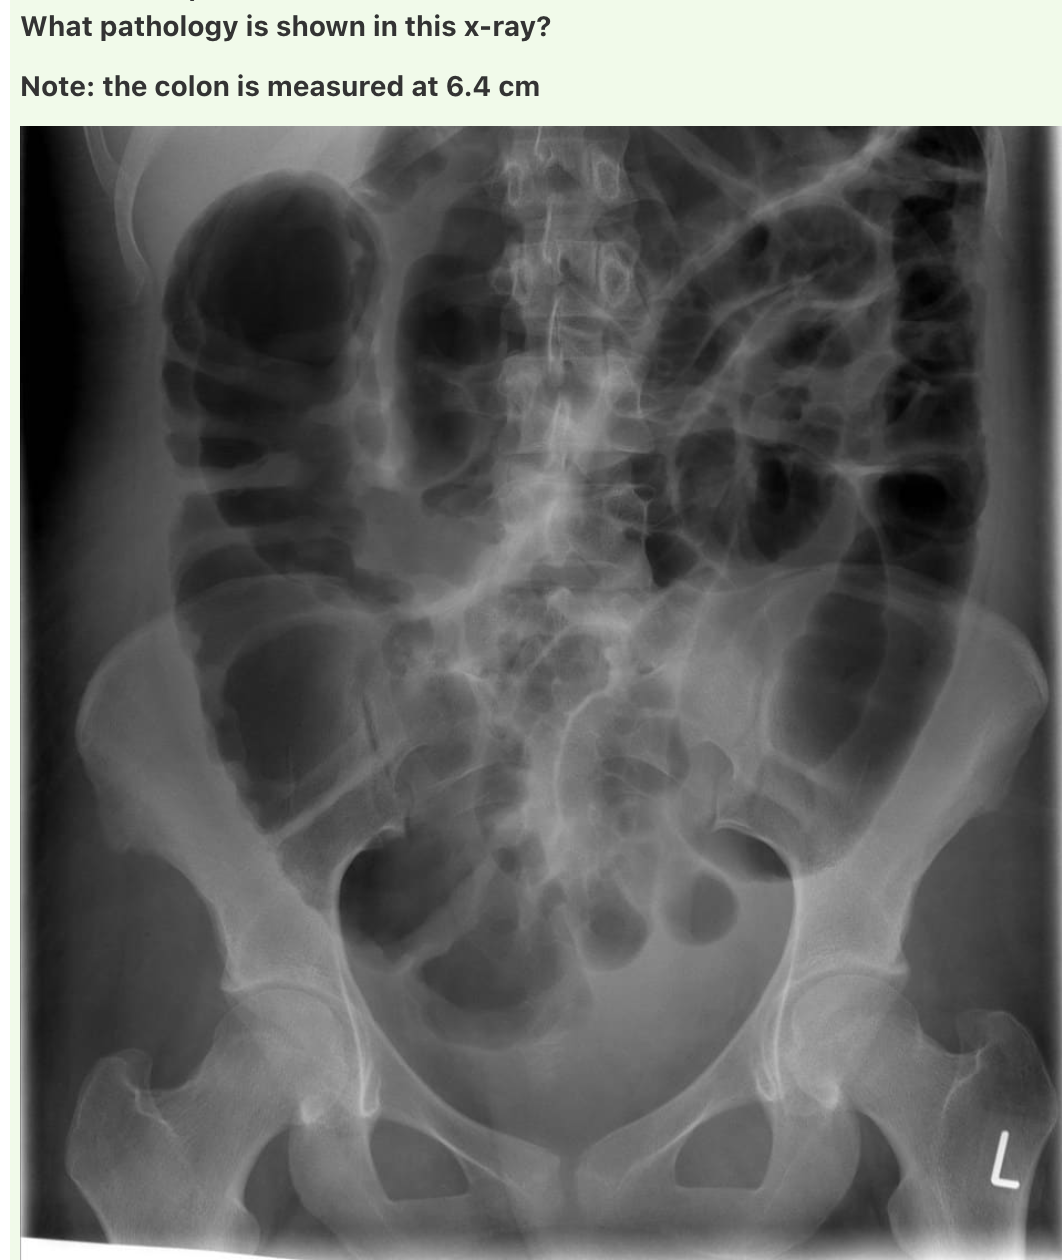

Answer: Toxic megacolon

A maximum colonic diameter greater than 6cm is considered consistent with toxic megacolon.